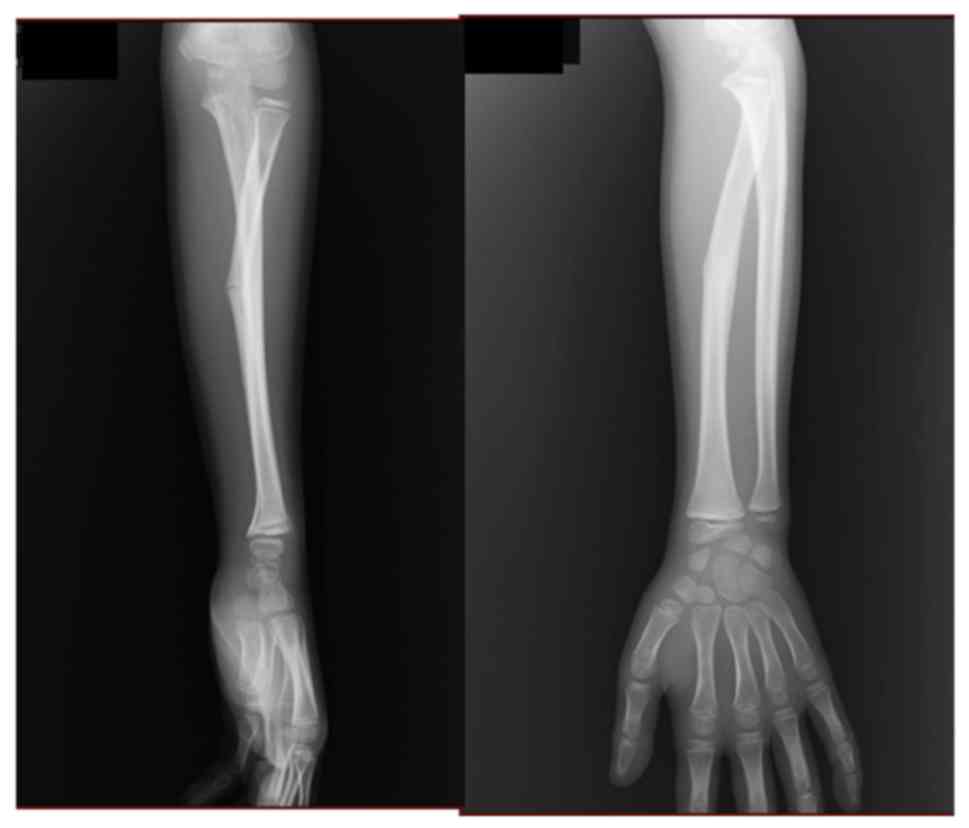

It is rare to find a fracture not uniting in case of fractures in children and whenever it occurs, there would be a strong reason for it like infection or some other pathology. Broken bones or fractures are common in childhood, with up to 40 percent of girls and as many as 50 percent of boys experiencing a fracture. This occurs when the ulna has a fracture and the radial head (the part of the radius near the elbow) has dislocated from the elbow joint.

Your child's treatment plan is determined by the type, location, and severity of the fracture. Fracture of a single bone with plastic deformation of the other bone. Some likely fractures your child may get include in sixty per cent of the cases, only the ulna bone is affected. The radial head is dislocated anteriorly and the ulna has a short oblique or greenstick fracture in the diaphyseal or proximal metaphyseal area.